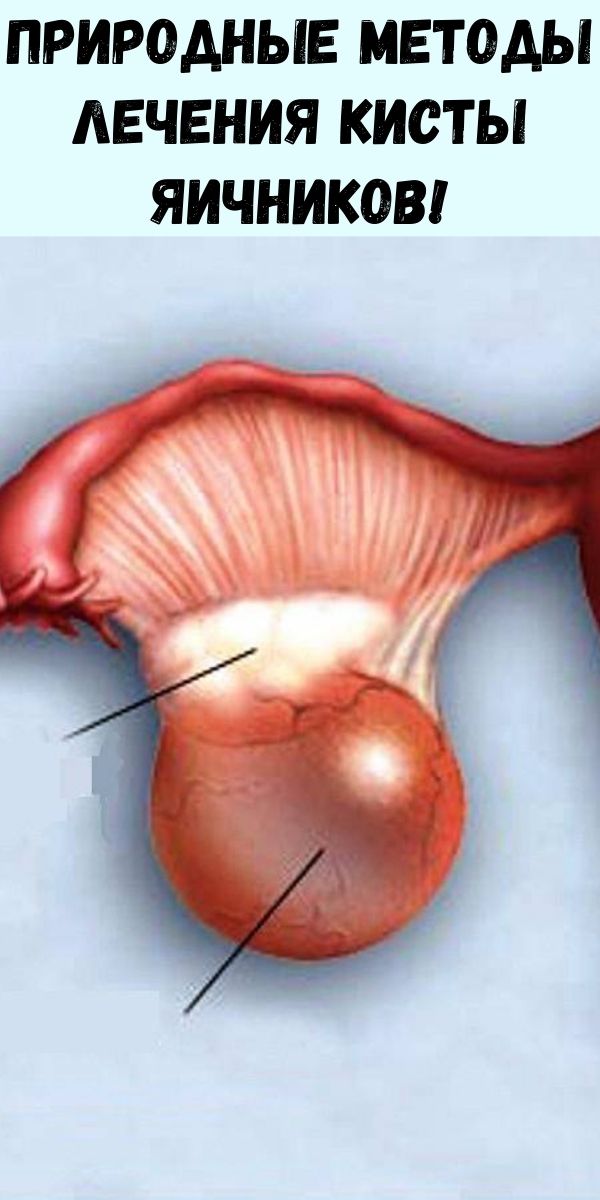

Гистологические изображения фолликулярной кисты яичника